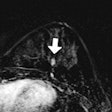

CAD becomes a spell-check for small polyps